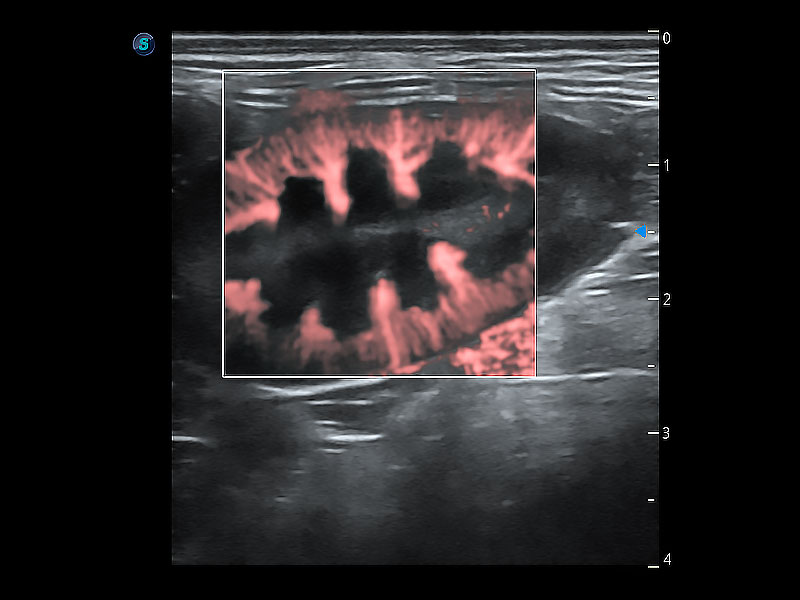

• Micro F 显微血流成像

极大提升超低速微细血流的检出能力,同时更精准地滤除软组织和超声信号,为兽用医生提供以往无法通过常规血流获得的疾病诊断信息。

(猫)胆囊

(犬)肾脏显微血流